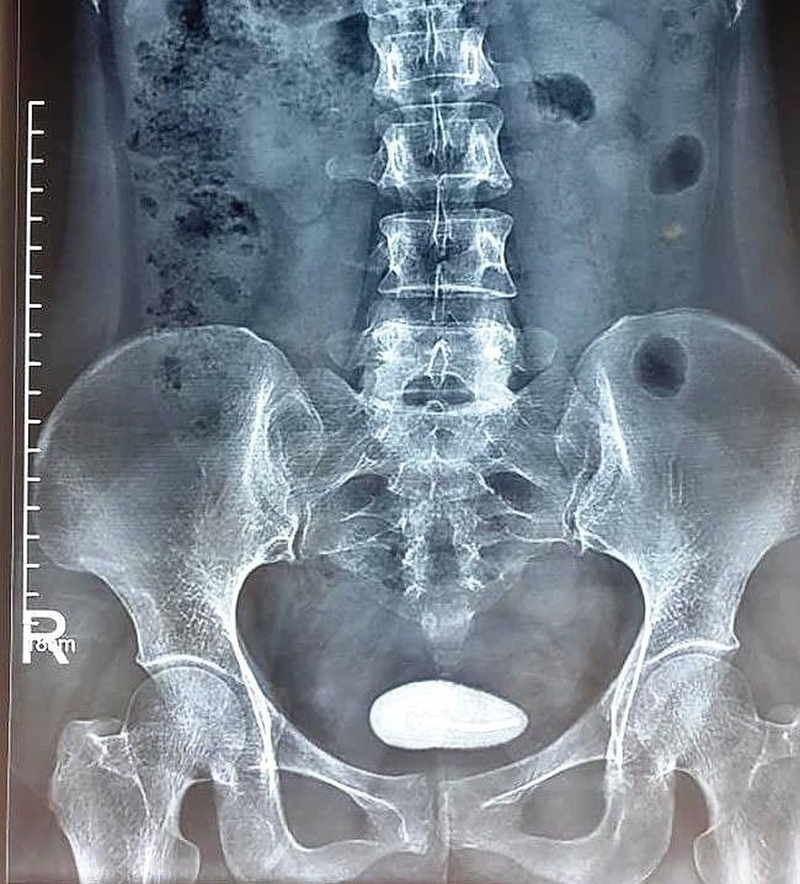

Để biết chính xác bé có bị sỏi thận hay không, bác sĩ thường sử dụng những phương pháp sau:

- Chụp X-quang;

Chụp X-quang để xác định bé có bị sỏi thận hay không.

Một số bé có thể sẽ gặp khó khăn khi mô tả triệu chứng và thường chỉ nói chung chung là mình bị đau bụng. Những bé quá nhỏ thì phụ huynh có thể cho con chụp X-quang hoặc kiểm tra nhiễm trùng đường tiết niệu.